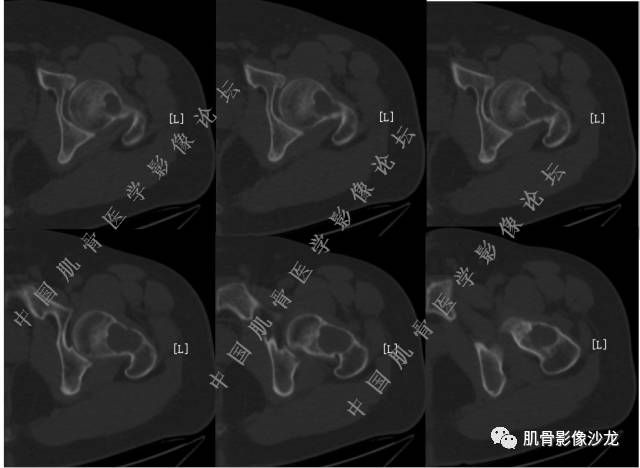

主诉:右髋及右膝部疼痛3月余

现病史:3月前打球时自觉右大腿肌肉拉伤后右髋及右膝部疼痛,自服“活血化瘀”类药物(具体不详)后自觉疼痛缓解,2月前打球时再次扭伤,右髋及右膝部疼痛明显,行走时疼痛加重,自服药物治疗,效果不佳,遂来诊。

医影在线 20:13 干骺端溶骨性破坏,边缘模糊,低密度肿块,似有钙化

Echo 20:13 有骨质破坏,边界不清,有软组织肿块,我觉得恶性是要考虑的

Echo 20:16 软组织肿块突破了骨皮质

Echo 20:23 我个人觉得,17岁男性,病灶发生在原干骺端区域,溶骨性骨质破坏,似有肿瘤骨,有软组织肿块形成,从常见病发生率来说,骨肉瘤还是要考虑的